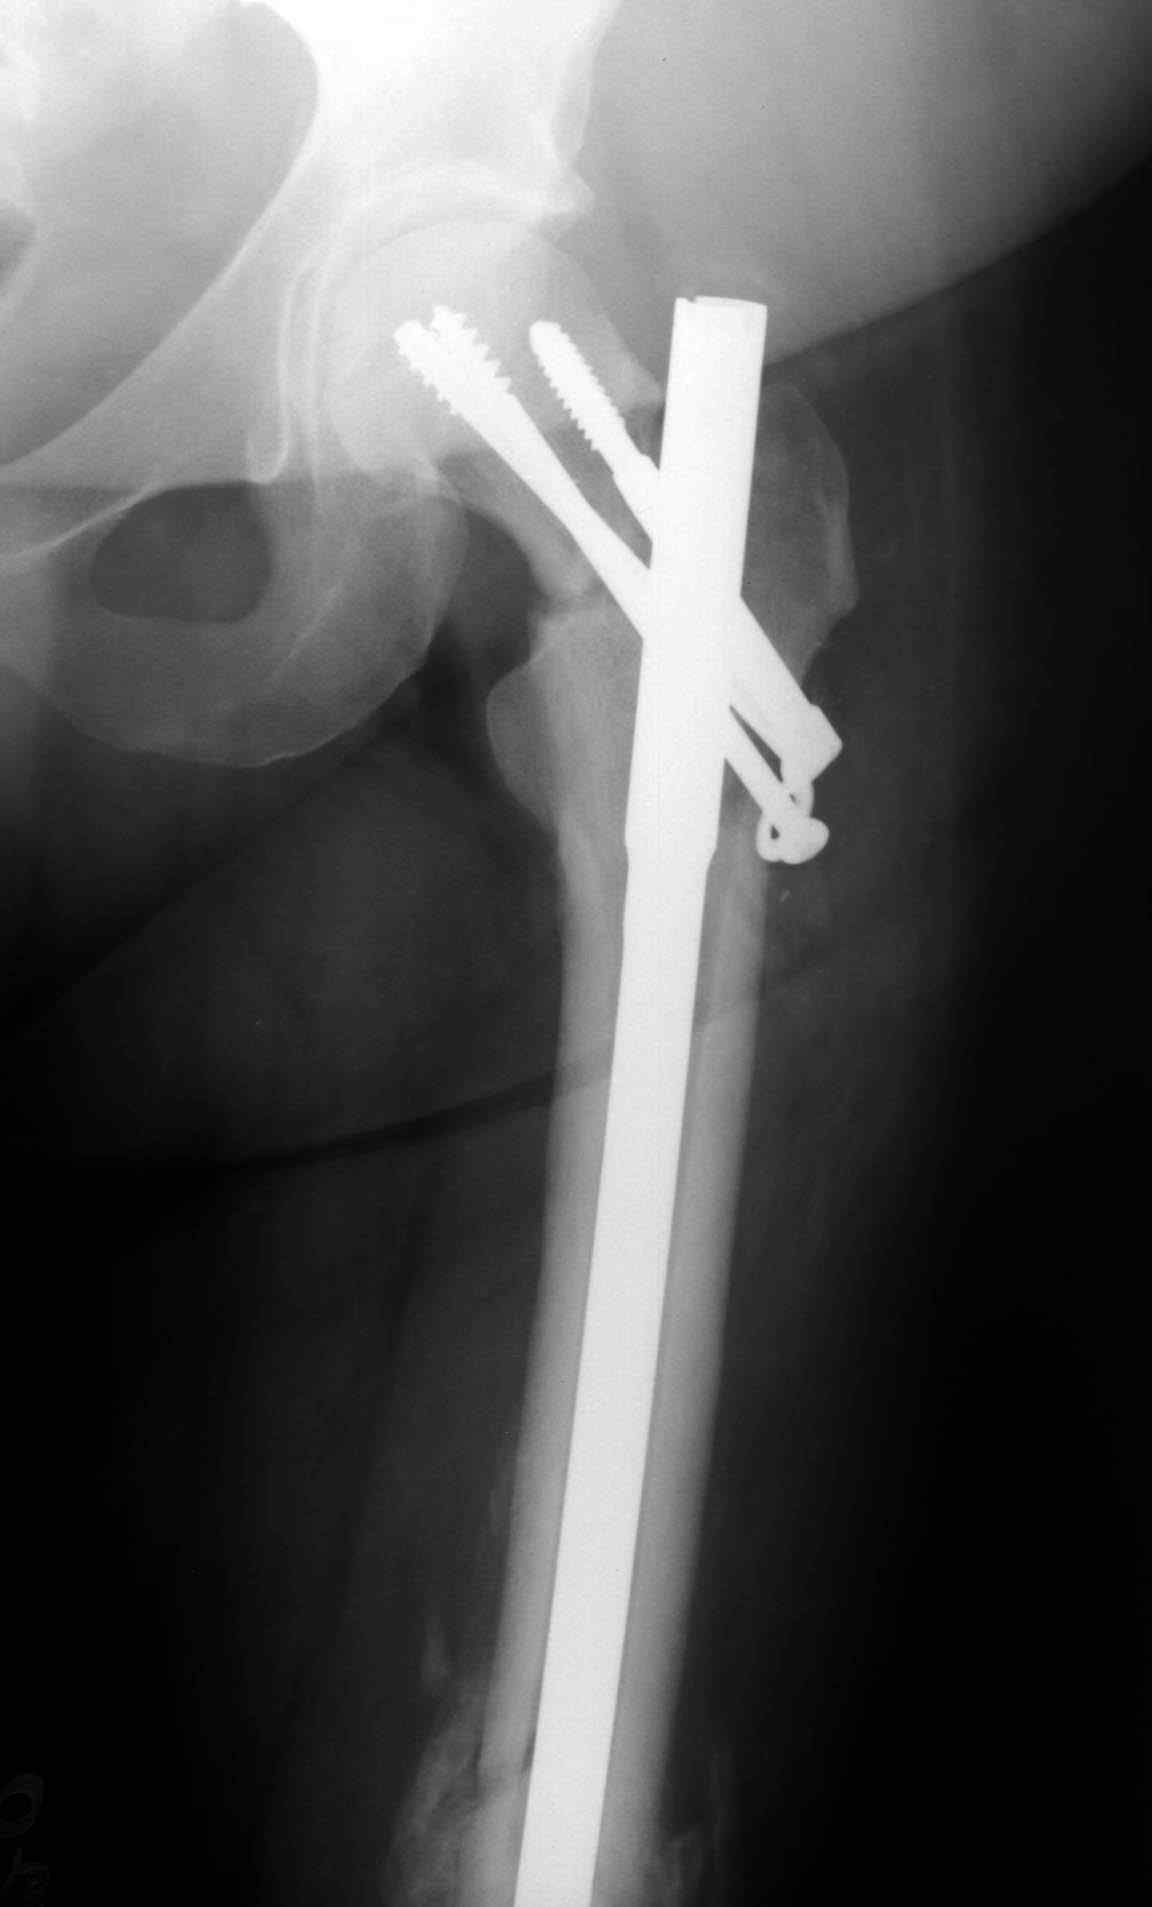

Ошибки случаются, когда игнорируются правила обследования больных с переломом бедра. Часто, когда "экономят" рентген пленки и снимают без надлежащих захватов сустава.

Одним из "золотых" правил при лечении переломов бедра в обязательном порядке до операции необходимо убедиться в отсутствии или наличии перелома шейки.

Отдельный снимок шейки или ЭОП является стандартом обследования. Все сомнительные рентген снимки проверяются тщательно дополнительными срезами КТ.

Из-за опасности вторичного смещения переломов "без смещения" во время интрамедуллярных манипуляций, особенно при ретроградном введении, необходимо каждый случай протоколировать с описанием состояния шейки после операции.

А не опорная болтающаяся конечность с большим рычагом усложнит состояние перелома шейки и поэтому ипсилатеральные переломы, тем более ятрогенные, очень часто осложняются двойными ложными суставами.